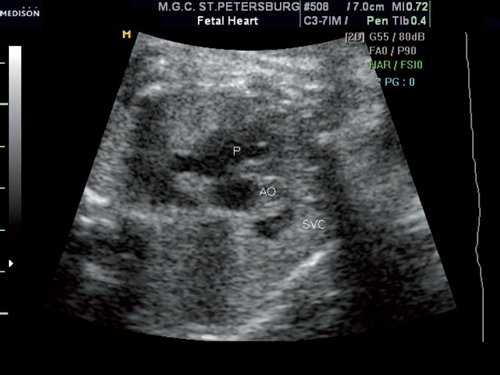

Повторный осмотр сердца плода проведен в 32 недели беременности. При оценке сердца и магистральных сосудов в стандартных сечениях сохранялась типичная ультразвуковая картина (рис. 1).

Рис. 1. Поперечное сечение грудной клетки плода на уровне среза через три сосуда.

Выше среза через три сосуда в передней трети грудной клетки визуализировался сосуд, размеры которого были сопоставимы с размерами верхней полой вены (рис. 2).

Рис. 2. Поперечное сечение грудной клетки плода выше уровня трех сосудов. Обращает на себя внимание крупный сосуд, располагающийся в передней трети грудной клетки.